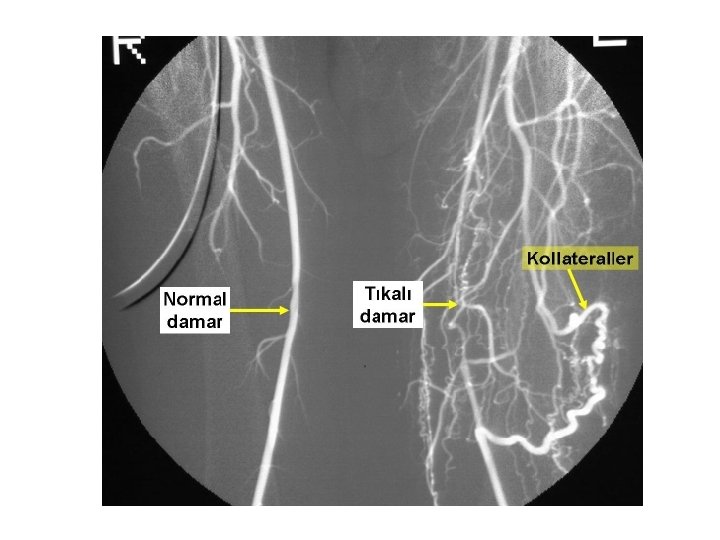

PERİFERİK ARTER HASTALIĞI NASIL GELİŞİR? • Darlık çok daha ilerlediğinde ise iç yüzeyde pıhtı oluşup, kan akımı tamamen durur. Bu durum ani olarak gelişmiş ise dokuların ani ölümüne yani gangrene yol açar ve acil olarak tedavi gerekir. Eğer bu durum belirli bir zaman içinde oluşmuş ise gelişen yan dallar, tıkanıklığın ilerisine canlılığı bir süre daha devam ettirecek ölçüde kan akımını sağlarlar (Kollateral gelişimi)